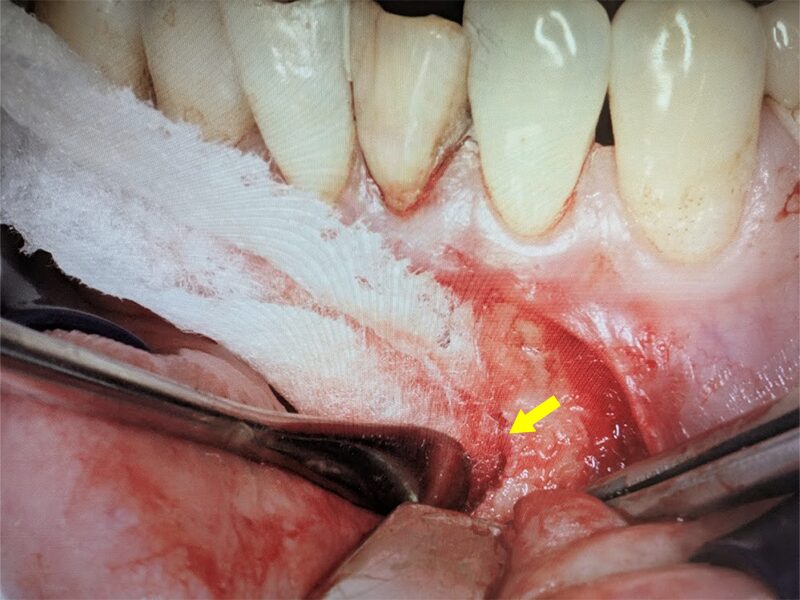

骨内で嚢胞の剥離を進めます。

嚢胞を摘出します。